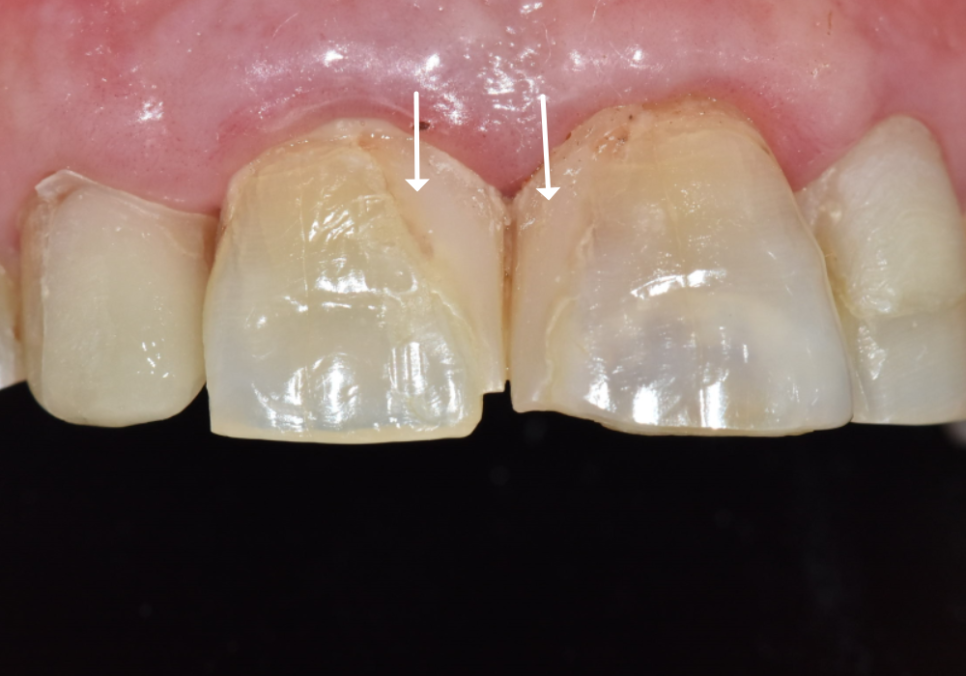

이 경우에는 반점 범위가 넓고

색 차이가 뚜렷했기 때문에,

미백을 진행하면

전체 치아는 밝아질 수 있어도

반점 부위는 오히려

더 도드라져 보일 가능성이 높았습니다.

그래서 미백은

현실적인 해결 방법이 되기

어렵다고 판단했습니다.

다만 앞니 전반에

반점이 분포된 경우에는

여러 면에 레진을 적용해야 하고,

시간이 지나면서

변색이 생길 가능성도

고려해야 합니다.